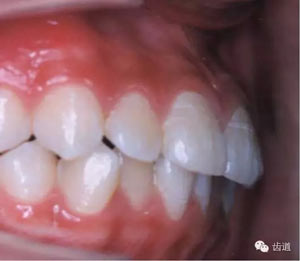

1.上下牙弓的長(zhǎng)度(近遠(yuǎn)中)關(guān)系

1)、第一恒磨牙的合關(guān)系:中性合、近中合或遠(yuǎn)中合

77.jpg

2)、上下前牙間的覆蓋關(guān)系:有否深覆蓋或反覆蓋

3)、上下牙弓的突度是否正常:有否雙牙弓前突。

82.jpg

83.jpg

2.上下牙弓的寬度關(guān)系

上下牙弓寬度是否協(xié)調(diào),上下后部牙弓有否對(duì)合、反合或鎖合。